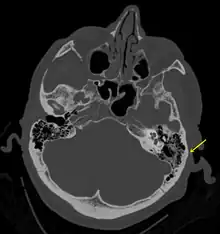

| A subtle temporal bone fracture as seen on a CT scan | |

Basilar skull fractures include breaks in the posterior skull base or anterior skull base. The former involve the occipital bone, temporal bone, and portions of the sphenoid bone; the latter, superior portions of the sphenoid and ethmoid bones. The temporal bone fracture is encountered in 75% of all basilar skull fractures and may be longitudinal, transverse or mixed, depending on the course of the fracture line in relation to the longitudinal axis of the pyramid.[5]

Temporal bone fractures

Acute injury to the internal carotid artery (carotid dissection, occlusion, pseudoaneurysm formation) may be asymptomatic or result in life-threatening bleeding. They are almost exclusively observed when the carotid canal is fractured, although only a minority of carotid canal fractures result in vascular injury. Involvement of the petrous segment of the carotid canal is associated with a relatively high incidence of carotid injury.[9]